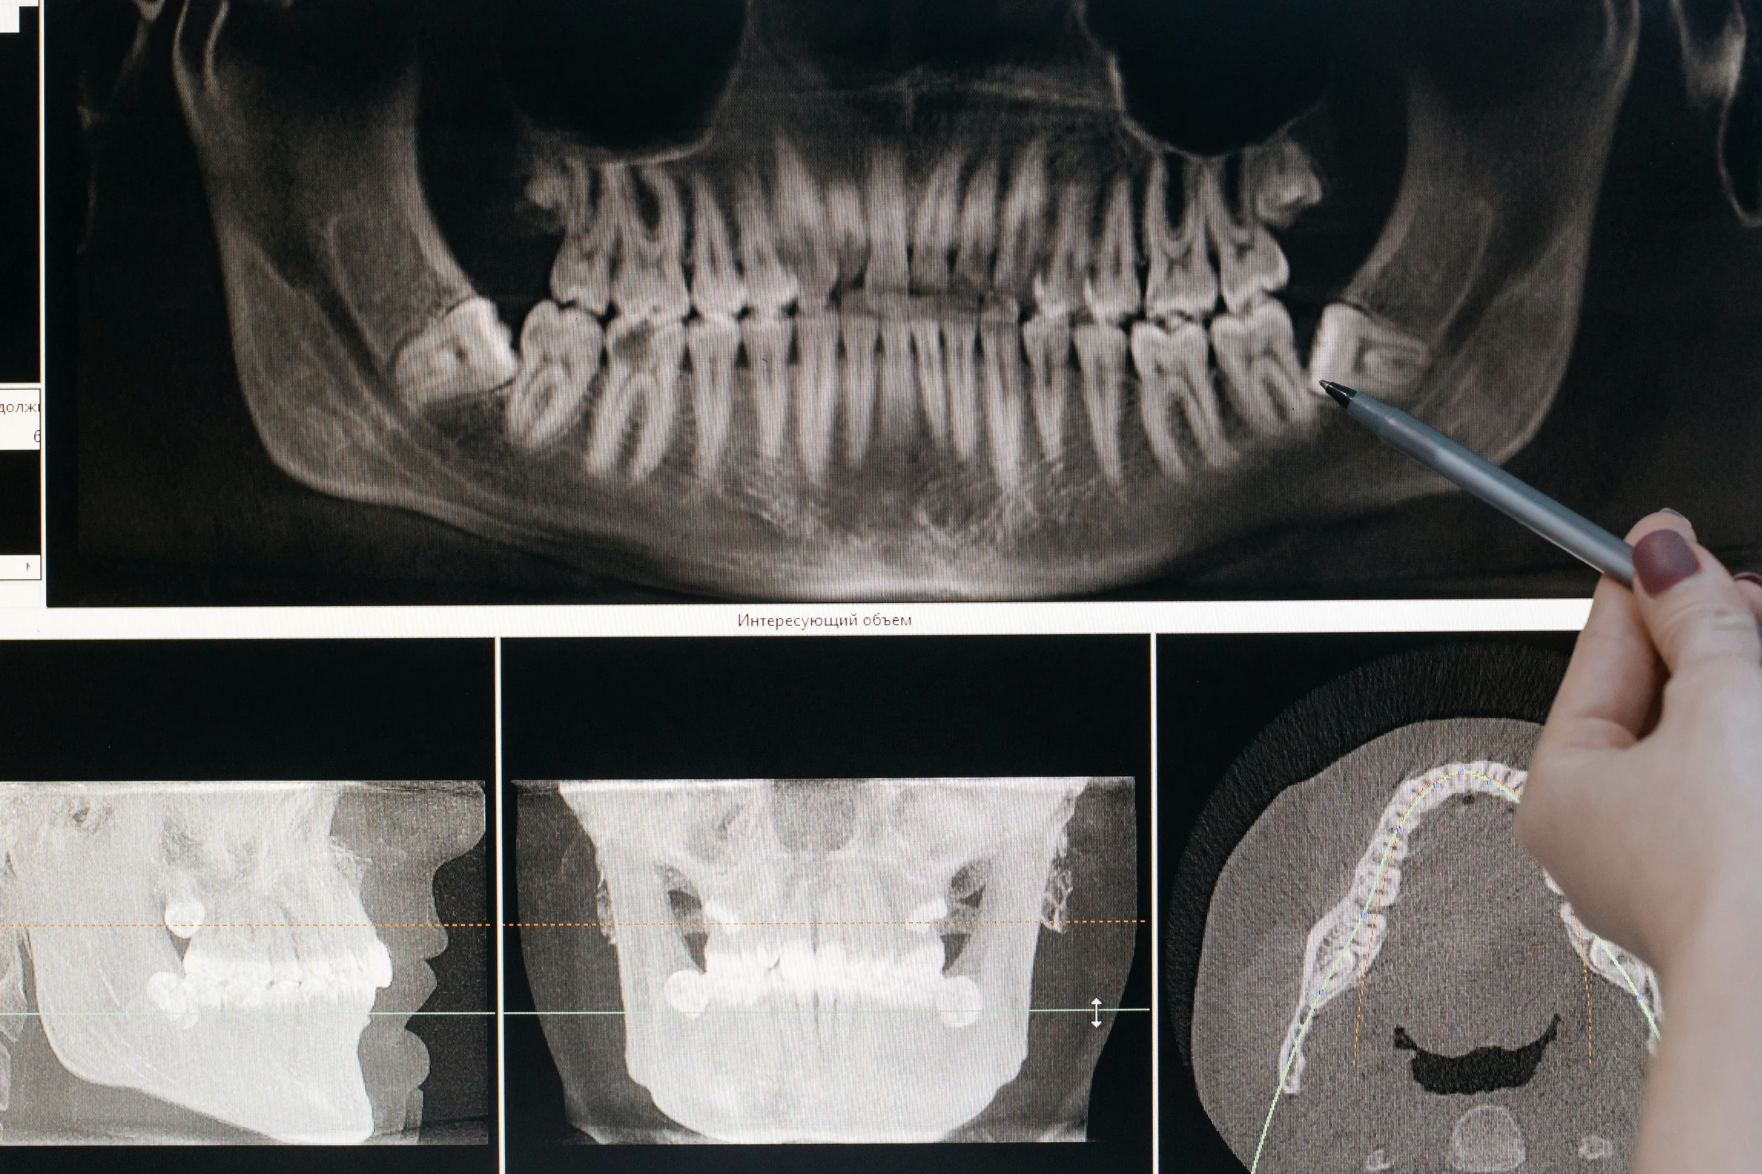

親知らずが骨の中に埋まっているような難症例では、親知らずの根が下顎を通る神経の束(下顎管)に接している場合があり、CT撮影にて3次元的に親知らずと下顎管の距離を把握することが大切です。

当院にはCT撮影が可能なレントゲンがあるため、大学病院に紹介されるような難易度の高い親知らずの抜歯も安全に行えます。

歯科用CT